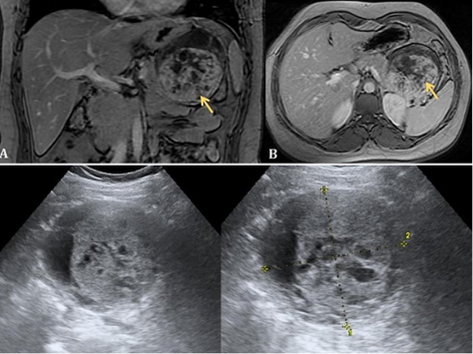

29-year-old female  long- standing abdominal pain localized to the left upper quadrant. Abdominal CT examination  well-encapsulated mixed density lesion of the pancreatic tail, with cystic central component and the peripheral hyperdense solid portion that slightly enhances on post- contrast images. US demonstrating a well-circumscribed, 70mm, encapsulated mass in the pancreatic tail, with heterogeneous mixed solid and cystic content.

EUS-FNA was performed with  low viscosity, bloody and necrotic, PAS and vimentin positive.

Which is the most likely diagnosis?